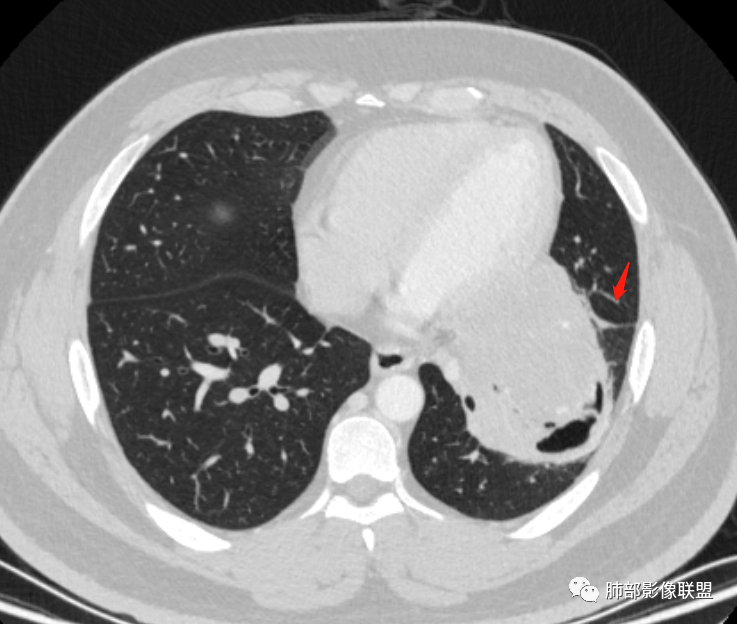

骑跨在斜裂上

局部斜裂稍增厚

下叶基底干支气管受压下移

下叶背段支气管受压稍后内移位,通畅

就是支气管目前基本没有堵塞,只是受压

空气新月征:

新月征很有特点,血管有特点

青年男性,体检发现左肺不规则类圆形占位性病变,叶间裂区域,定位胸膜来源。左肺下叶支气管受压狭窄,但管壁光整,未见腔内阻塞或管壁受侵。包块边界清晰,浅分叶,内部密度不均匀,病灶后份见空气新月征。渐进性强化,增强动脉期见分支状血管,蛇纹血管征。肺门纵膈未见增大淋巴结,符合孤立性纤维瘤(SFT)。